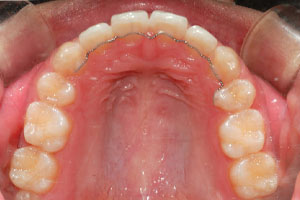

치료증례 전후사진

Before & After

a9db3067cff1c27c28aa713ee7f36abc_1698976199_9893.jpg